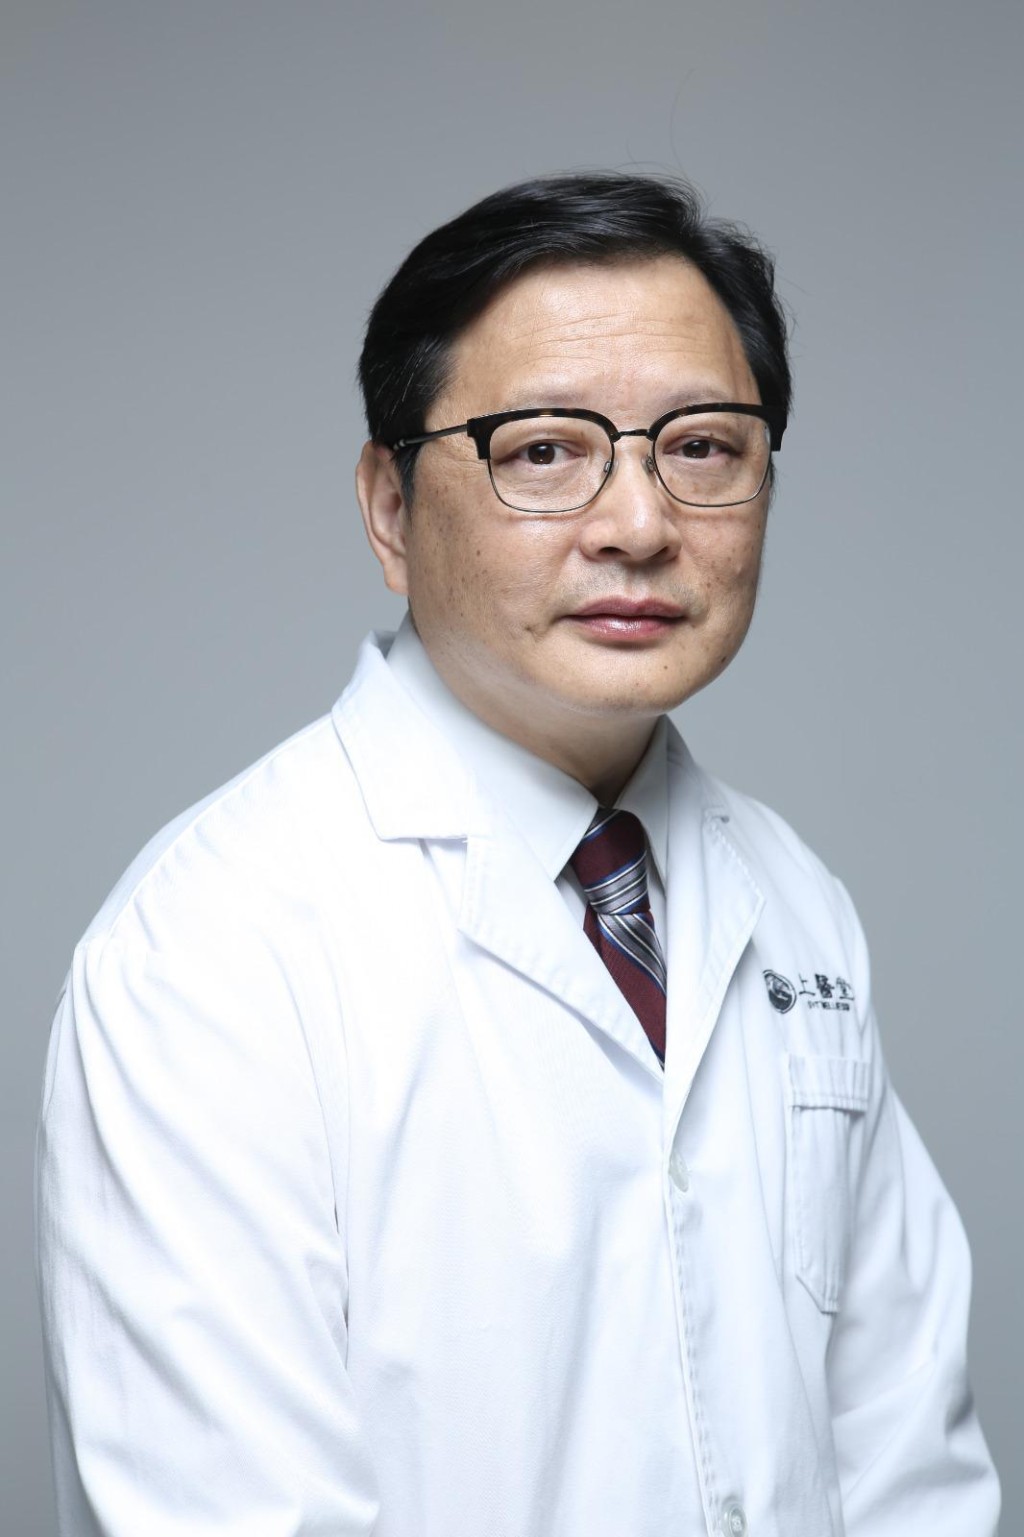

上醫堂創辦人張勇說:「夏季指農曆立夏、小滿、芒種、夏至、小暑、大暑等六個節氣,即農曆四月、五月、六月。氣候特點炎熱,陽氣旺盛,酷暑蒸人。中醫經典著作《黃帝內經.素問四氣調神大論》中提到『夏三月,此謂蕃秀』。『蕃秀』的含義就是茂盛、華美的意思。也就是說,夏季氣候炎熱,陽氣旺盛,萬物茂盛。在香港,夏季除了氣候從溫轉熱之外,經常下雨,時而細雨綿綿,時而狂風暴雨、雷電交加,濕氣尤盛,地板、牆壁皆可見水珠,而在六至八月間則可能是碧空萬里,望不到雲的炎熱天氣,常常給人們熱不可耐,煩躁不安的感覺。」

着重健脾益胃

夏天氣候炎熱,人們汗流如注,不但損耗大量體液,還消耗體內各種營養物質,尤其是無機鹽類,如不及時補充,可發生體液失調及代謝紊亂情況。同時,天熱影響脾胃消化功能,加上睡眠不足、損耗津液,大大地減弱了食欲,許多人在夏季時體重都有不同程度的下降。因此,飲食方面於注重化濕消暑的同時,健脾益胃也是不可忽視的。人言夏日不宜進補,其實不然,俗語指「夏天進補,冬天打虎」,夏季調補得當,使氣血化源充足,人體才能充滿活力,以保健康。

智吃蔬菜瓜果

夏季進補,一是補充損耗的物質,二是供給機體的需要,維持正常的生理活動功能。補品應以清淡芳香為主。清淡易消化,芳香刺激食欲,如魚類、各種動物的瘦肉、禽蛋、淮山、蓮子、苡仁等;乳製品、豆類及新鮮蔬菜、水果、海帶、紫菜等,均宜適量多食,肥甘厚味的肉類或其他難以消化的補品宜少食。此外,還可適當吃些瓜果冷飲,以起降溫防暑的作用,例如西瓜、鳳梨、蘋果、綠豆湯、南瓜湯等,特別是新鮮果汁如橙汁、檸檬汁、番茄汁等,營養豐富,幫助消化,又能促進食欲;同時也可飲一些熱茶,以利清暑熱、提升精神。總之,夏季調補應注意易於消化、富於營養,否則過於肥膩、過於燥熱或過於寒涼,勢必影響脾胃而造成脾胃功能紊亂,出現噁心、嘔吐、腹瀉等症狀。